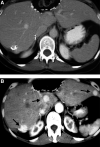

New guidelines to evaluate the response to treatment in solid tumors using imaging techniques have major limitations and important implications for radiological workload. This consensus statement from the International Cancer Imaging Society (ICIS) reviews the RECIST criteria and addresses several challenges regarding tumour measurement. Recommendations are made regarding tumour measurement and other issues are raised. The growing need to introduce a multimodality approach to monitoring response is recognized. ICIS welcomes a dialogue with the authors of RECIST to address issues raised in this review.